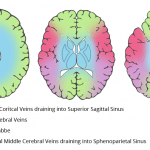

- Multiple areas of segmental thrombus in the nondominant left transverse sinus with occlusive thrombus extending from the transverse-sigmoid sinus junction into the left internal jugular vein

- Lack of opacification of the bilateral cavernous sinuses

- Nonopacified, engorged left superior ophthalmic vein

- Nonocclusive filling defect in the right jugular bulb

- Dural venous and cavernous sinus thrombosis

Dural venous sinus thrombosis with multiple areas of segmental thrombus in the nondominant left transverse sinus and occlusive thrombus extending from the transverse-sigmoid sinus junction into the left internal jugular vein. Lack of opacification of the bilateral cavernous sinuses is concerning for bilateral cavernous sinus thrombosis. There is also thrombosis of the left superior ophthalmic vein and nonocclusive thrombus in the right jugular bulb. No acute hemorrhage or mass effect.